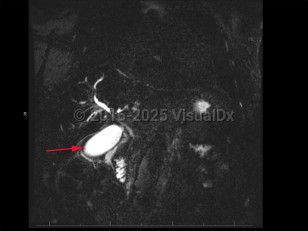

Cholangiocarcinoma refers to biliary tree malignancies, primarily adenocarcinomas, of epithelial cell origin. They are typically categorized as intrahepatic, perihilar, or distal.

Cholangiocarcinomas often present insidiously; symptom onset often coincides with biliary duct obstruction leading to jaundice, pruritus, or cholangitis. Other less specific signs and symptoms include unexplained weight loss, lethargy, abdominal pain, nausea, and anorexia.